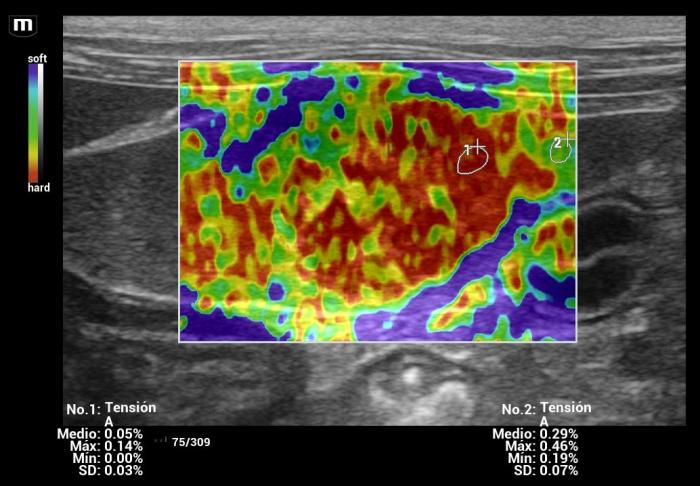

Además de la medición cuantitativa de la velocidad de la onda de corte expresada en metros por segundo (m/s), el sistema Natural Touch Elastography® (Mindray MX7) dispone de una función complementaria de representación cualitativa y semicuantitativa de la rigidez tisular (Figura1-4). Esta herramienta permite asignar valores numéricos y porcentajes relativos al grado de dureza o blandura del tejido evaluado y facilita la comparación visual y numérica entre diferentes regiones de interés dentro de un mismo órgano, incluyendo la relación entre una lesión focal y el parénquima esplénico adyacente.

De acuerdo con la documentación técnica del fabricante, esta funcionalidad se basa en el análisis de la respuesta tisular al impulso acústico y en algoritmos de seguimiento por radiofrecuencia, lo que contribuye a una evaluación intraorgánica más precisa. Si bien estos valores no sustituyen las mediciones cuantitativas en m/s ni cuentan con puntos de corte validados para la diferenciación diagnóstica, su utilización aporta información complementaria útil para la interpretación clínica de los hallazgos elastográficos, especialmente cuando se integra con la evaluación en modo B y Doppler.

Hallazgos elastográficos (Natural Touch Elastography®): la lesión mostró una rigidez similar al parénquima esplénico circundante, con valores que no superaban los rangos normales descritos para bazo canino3,4 (Figura 9-10). La uniformidad de las mediciones, sin artefactos relevantes y con estabilidad entre adquisiciones consecutivas, aumentó la confiabilidad de la evaluación.

Hallazgos elastográficos (Natural Touch Elastography®): la lesión de mayor tamaño mostró rigidez elevada, significativamente superior al parénquima esplénico normal (Figura21-22).

Este comportamiento coincide con el patrón elastográfico típico de lesiones malignas descrito en la literatura5, donde los tumores esplénicos (incluyendo hemangiosarcoma) tienden a presentar velocidades de onda de corte superiores a las de lesiones benignas.

Hallazgos elastográficos (Natural Touch Elastography®): el nódulo presentó una rigidez marcadamente aumentada respecto del parénquima esplénico circundante, con patrón elastográfico heterogéneo (“dureza mixta”), caracterizado por áreas internas de elevada velocidad de onda de corte (Figura 26-27).

Este comportamiento se alinea con los hallazgos reportados para lesiones malignas esplénicas, que tienden a presentar valores superiores a 3 m/s según la evidencia publicada5.